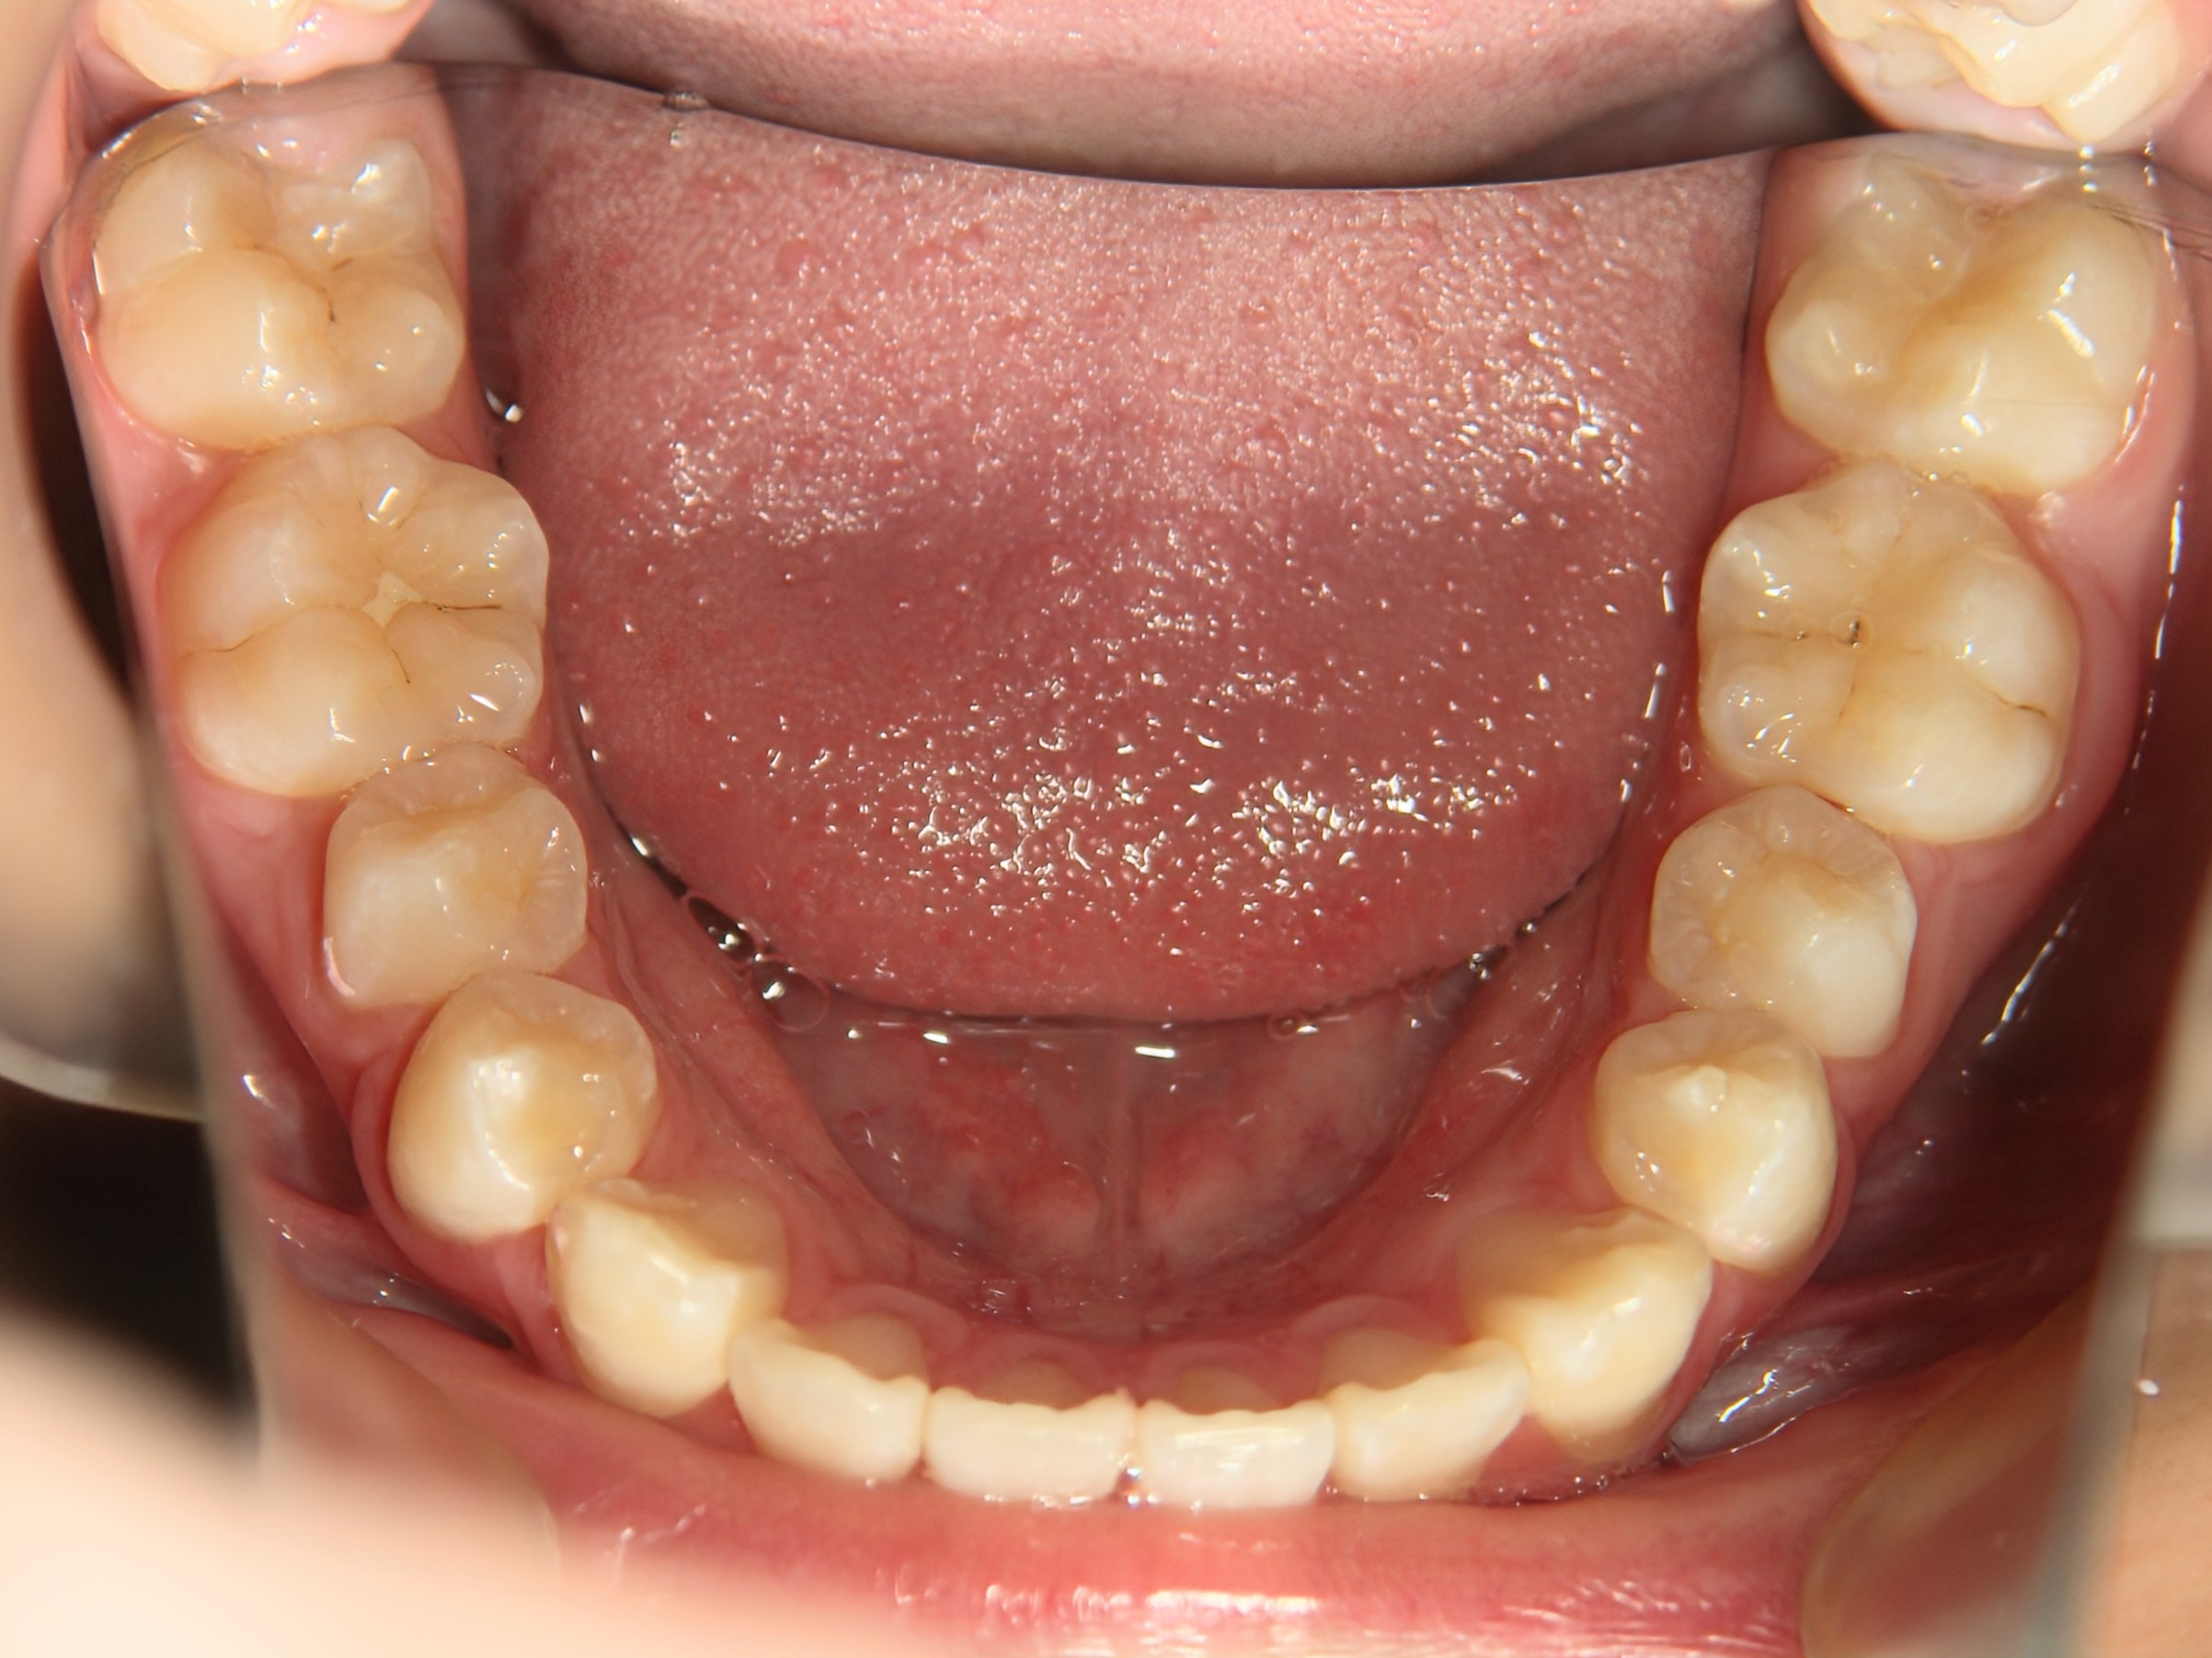

第1期治療開始時

顔貌写真

口腔内写真

年齢

9歳 男性

主訴(患者様のお悩み)

歯のデコボコを治したい

診断

上顎前歯部叢生(上の前歯のデコボコ)

上下顎側切歯クロスバイト(部分受け口)

上顎狭窄歯列(上のあごが小さめ)

歯冠幅径大(歯が大きめ)

治療方針

上顎緩徐拡大(上あごを拡大)

上の前歯部のみワイヤー矯正

使用装置

緩徐拡大装置(クワドヘリックス)

前歯部ブラケット

治療期間の目安:約半年~1年(保定期間を除いた期間)